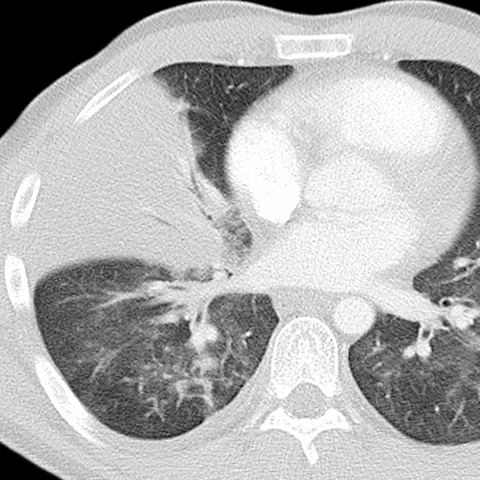

Silhouette Sign, RML Pneumonia (Chest CT) [3 of 4]